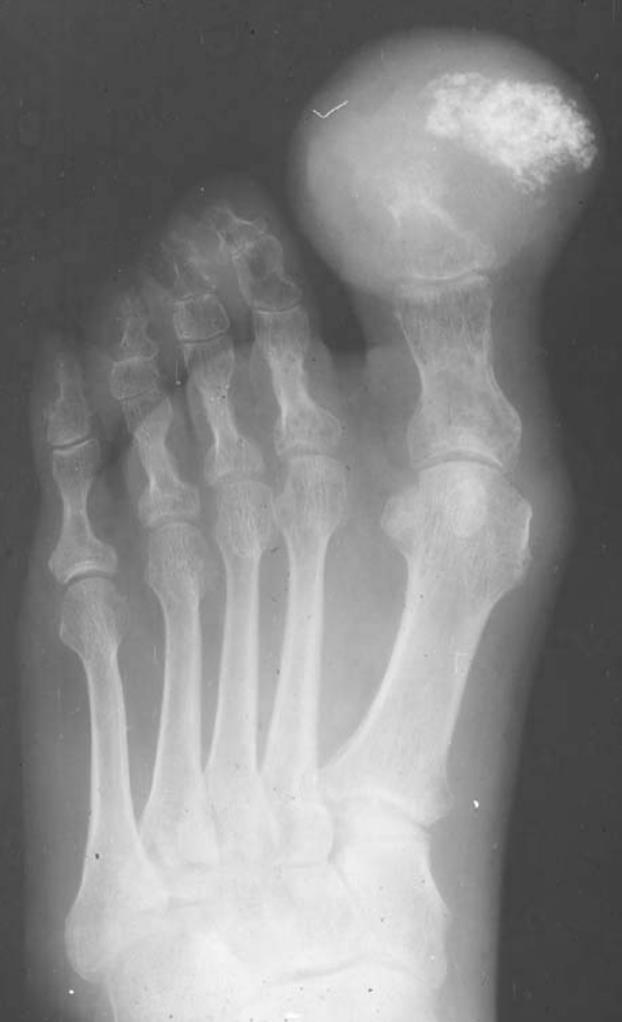

Synovial Sarcoma

• it is the most common sarcoma of the foot

• Radiographs

• can show soft tissue mineralization (calcification) in these tumors

• may resemble heterotopic ossification